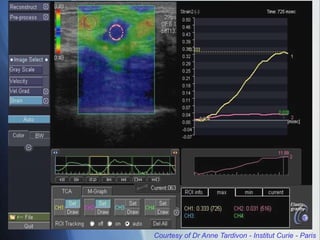

Courtesy of DrAnne Tardivon - Institut Curie - Paris Elastography: improvements  Compression/Decompression Movements  Displacement speed measurement  Integral -> Elasticity  Elasto Q Mode  Information at decompression  Automatic selection of the best cycle  ROI on fat and lesion  Quantification

Elastography: improvements

 Compression/Decompression Movements

 Displacement speed measurement

 Integral -> Elasticity

 Elasto Q Mode

 Information at decompression

 Automatic selection of the best cycle

 ROI on fat and lesion

 Quantification